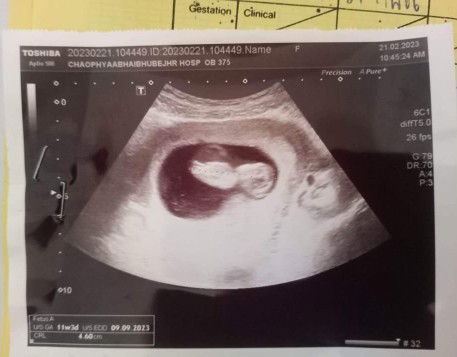

มาอวดใบซาวด์กันค่า

8w ☺️☺️👶👶